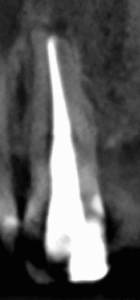

根管充填した。

Gutta Percha Pointは#60.02か#50.04であろう。

どちらがより適しているだろうか?

術後にPA,CBCTを撮影した。